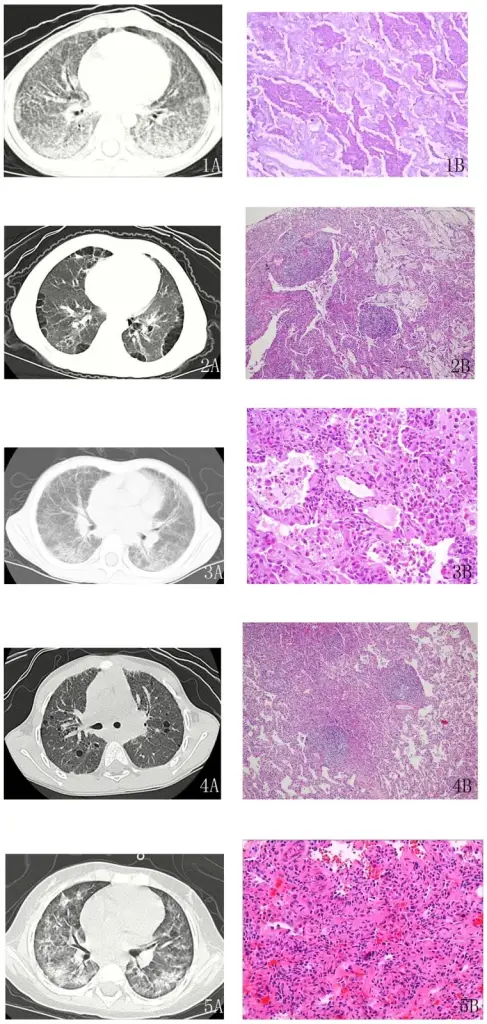

Three common patterns of pneumonia may be detected on chest X-ray which include:

- Lobar pneumonia

- Bronchopneumonia

- Interstitial pneumonia

Lobar Pneumonia

Lobar pneumonia is characterized by the consolidation of a whole lung lobe.

Bronchopneumonia

Bronchopneumonia is characterized by patchy, sporadic consolidation, concentrated on the bronchioles.

Bronchopneumonia is frequently bilateral and multifocal.

Interstitial Pneumonia

Interstitial pneumonia is also known as atypical pneumonia.

Diffuse interstitial infiltrates are the defining features of interstitial pneumonia.